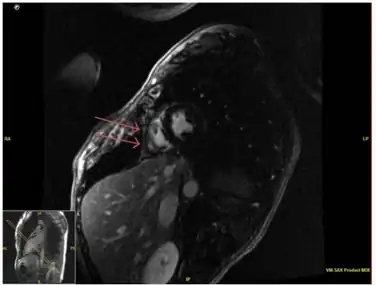

Pericardial enhancement of right ventricular free wall on cardiac MRI consistent with acute pericarditis. -